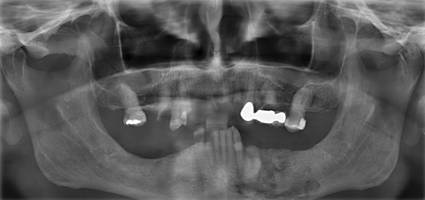

Osteomyelitis bedeutet „Knochenmarkentzündung“. Diese kann auch im Kiefer auftreten. Ursache kann z.B. eine „verschleppte“, lang andauernde bakterielle Knocheninfektion nach Entzündung um eine Zahnwurzel sein. Häufig kann die Ursache jedoch auch nicht mehr genau geklärt werden. Die Patienten klagen über leichte bis mittelstarke Schmerzen, Kribbelgefühle und / oder andere Missempfindungen im Kiefer, deren genaue Ausdehnung sich manchmal nur vage bestimmen lässt. Bei der Untersuchung findet sich als indirektes Zeichen häufig eine gerötete, druckschmerzhafte Schwellung am Kiefer als Zeichen der begleitenden Entzündung des umgebenden Weichgewebes. Wenn nur der Knochen betroffen ist, kann die Untersuchung auch völlig normal sein. Als Bildgebung kommen, angepasst an den jeweiligen Fall, Röntgenbilder, DVT (Digitales Volumentomogramm), CT, MRT und eine Szintigraphie in Frage. Hierdurch soll herausgefunden werden, ob und in welchem Ausmaß das Knochenmark entzündet ist.

Bei der Osteomyelitis ist eine genaue Untersuchung und sorgfältige Behandlung besonders wichtig, weil dieses Krankheitsbild noch nicht in allen Details verstanden ist und nur bei prompter und adäquater Behandlung die Chancen besteht, eine langwierige Erkrankung zu vermeiden.

Therapeutisch bietet das Universitätsklinikum Düsseldorf die nur an wenigen Standorten in Deutschland verfügbare Möglichkeit, mittels „hyperbarer Sauerstofftherapie“ (HBO=“ hyperbaric oxygen therapy“) den erkrankten Knochen zu behandeln. Durch die optimale Sauerstoffversorgung wird die Chance zur Aufteilung der Entzündung verbessert. Unterstützt wird diese Behandlung durch Antibiotikagabe zur Bekämpfung der krankheitserregenden Bakterien vor Ort. Wenn chirurgische Maßnahmen nicht zu vermeiden sind, müssen gegebenenfalls die entzündeten Knochenabschnitte angefräst (Dekortikation) oder entfernt werden. Resezierte Kieferabschnitte werden in derselben Operation oder später durch Knochentransplantate ersetzt.